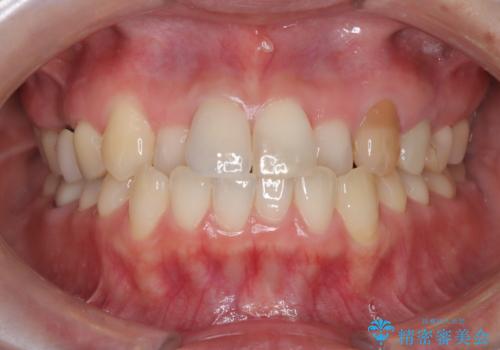

【オールセラミック】前歯の色を変えたい。

- 前歯の色が変色してきたことを主訴に来院されました。

根管治療から被せものまで治療を行いました。

オールセラミックは、透明感があり綺麗な色調を再現できます。